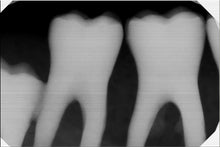

• Advanced CMOS sensor technology enhances image quality. • Captures high resolution images; providing more than 20 visible line pairs per millimeter. • Capabilities of a wide range of x-ray exposure settings to provides consistent image quality and consistent results • Rounded corners and smooth edge on the sensor for a comfortable fit. • Durable materials and components increase the life span of the product. • Direct USB Connectivity to computer. No docking stations or adapters required. • Lightweight and portable with hi-speed USB 2.0 connectivity for quick and easy use over multiple operatories. • An “Always Ready” feature that automatically recognizes radiation and starts image acquisition without the need to initiate through software. Visually inspected the unit for any damaged or missing parts and accessories. Function tested the unit and found it to be fully functional with good cosmetic condition.

• Advanced CMOS sensor technology enhances image quality. • Captures high resolution images; providing more than 20 visible line pairs per millimeter. • Capabilities of a wide range of x-ray exposure settings to provides consistent image quality and consistent results • Rounded corners and smooth edge on the sensor for a comfortable fit. • Durable materials and components increase the life span of the product. • Direct USB Connectivity to computer. No docking stations or adapters required. • Lightweight and portable with hi-speed USB 2.0 connectivity for quick and easy use over multiple operatories. • An “Always Ready” feature that automatically recognizes radiation and starts image acquisition without the need to initiate through software. Visually inspected the unit for any damaged or missing parts and accessories. Function tested the unit and found it to be fully functional with good cosmetic condition.